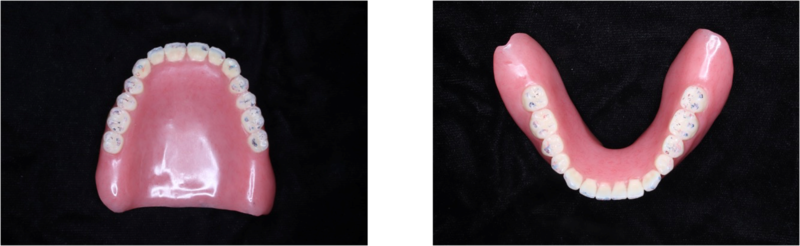

治療用義歯完成(保険)

治療用義歯の完成になります。上下左右ともにしっかりと噛んでいます。お口の中に入れてかみ合わせを調整して、セットしました。

この患者さんの治療用入れ歯(義歯)は、保険で作製しています。治療用入れ歯(義歯)は、多くの場合、保険で製作します。

6か月後→最終義歯製作

半年後に最終入れ歯(義歯)製作になります。患者さんよりこの入れ歯(義歯)が良く噛めて痛くないので、同じような入れ歯(義歯)と作って欲しいとリクエストがありました。

デジタルデンチャーセット

完成したデジタルデンチャーです!

非常に粘膜面のコピーが上手くいっており、入れ歯の形が非常に再現されています。

デジタルデンチャー(お口の中)

お口の中でも問題なくセットができました。外形の変化が少ないので違和感が少ないと考えました。